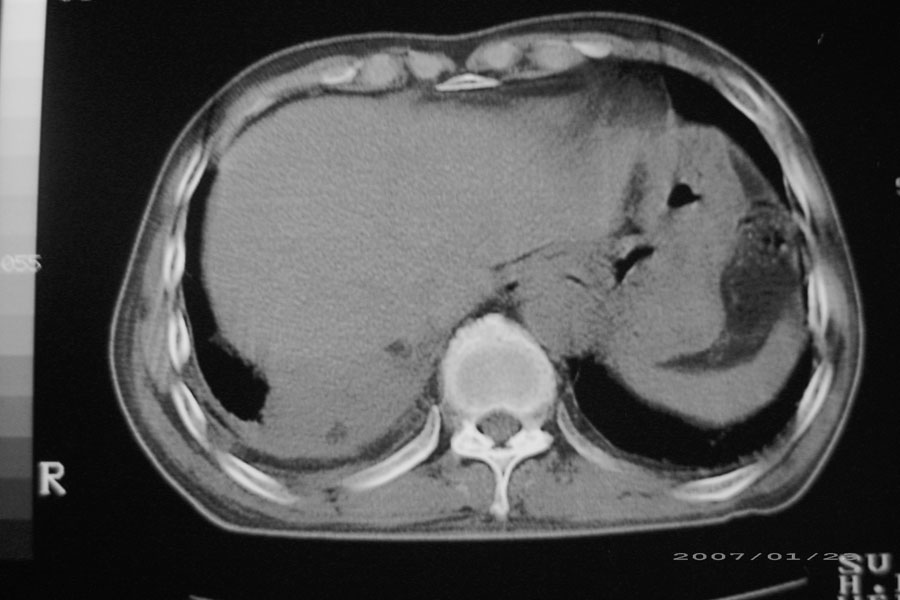

以下是引用天南地北在2007-1-24 18:00:00的发言:[br]1:右下肺内基底段类椭圆性肿快影:考虑1:右下球形肺炎2:右下肺隔离症,建议抗炎治疗后复查。[br]2:右肺及左下肺感染,右侧少量胸腔积液。

以下是引用hhcckk在2007-1-24 18:11:00的发言:[br]病灶周围胸膜反应比较明显,考虑炎症可能性大点,病人年龄较大,病灶成块状,肿瘤也不能排除,可可西里老师看片子的确很仔细,隔离肺暂时我觉得证据的说服力不大,上下层面显示条状影范围较长,可能是增厚的胸膜,可以做个增强鉴别一下